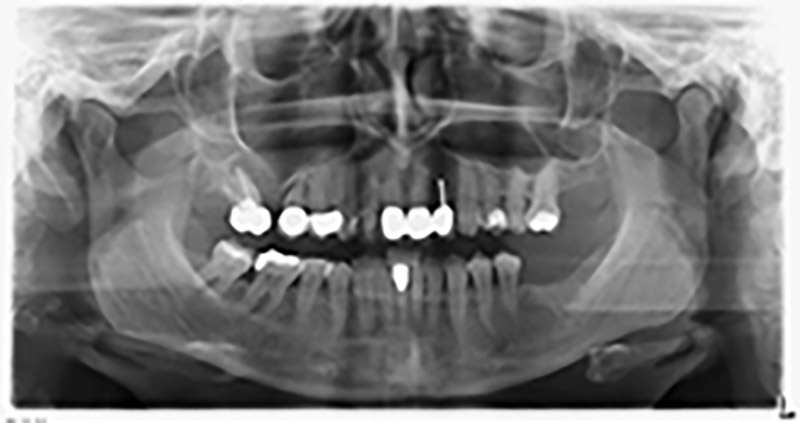

Шест месеца след екстракцията на зъби 16 и 14 се извършва преглед с дигитален томограф (DVT, Planmeca), с цел планиране и намаляване на възможните рискове. Ясно се вижда, че костта не се е регенерирала до желания обем (Фиг. 2 до 7).